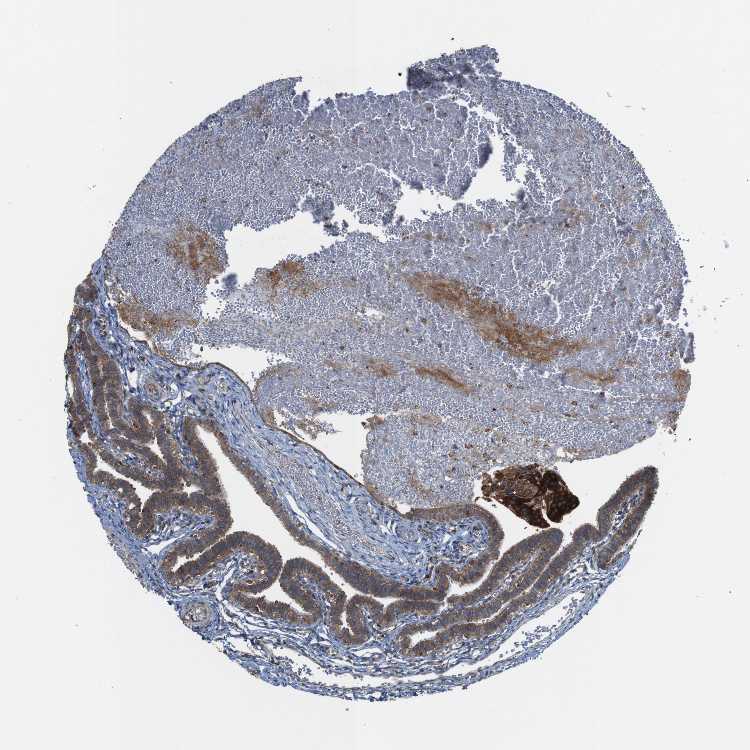

TISSUE PRIMARY DATA FALLOPIAN TUBE Show tissue menu

FALLOPIAN TUBE - Antibody stainingi

Antibody staining in the annotated cell types in the current human tissue is reported as not detected, low, medium, or high, based on conventional immunohistochemistry profiling in selected tissues. This score is based on the combination of the staining intensity and fraction of stained cells.

Each image is clickable and will lead to virtual microscopy that enables deeper exploration of all samples and also displays staining intensity scores, fraction scores and subcellular localization as well as patient and tissue information for each sample.

Antibody HPA012761Antibody HPA015127

Glandular cells MediumMedium